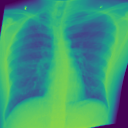

4.1.2 Lung Segmentation

Additionally, we evaluate the performance of DiffeoNN on real-world data, using a dataset with chest X-ray images and their ground-truth lung segmentation from (RSUA, 2023). The original dataset contains images and corresponding ground-truth segmentations into three different classes (“Non-Covid”, “Covid”, and “Non-Covid-Pneumonia”). We combine the images and corresponding ground-truth segmentations of the initial three classes into one dataset, which is then split into a training dataset of image-segmentation pairs, a validation dataset of pairs, and a test dataset of pairs. We then proceed as in Section 4.1.1 to create a dataset of diffeomorphically transformed images.

Benchmarking Results

We apply DiffeoNN, the inner U-Net (naïve approach) and an augmented U-Net, which is trained on the original and the diffeomorphically transformed training dataset, to the diffeomorphically transformed images from the test dataset. Visual results are presented in Figure 4 and further details on the experimental setup, training, and additional examples in Appendix B. The results closely mirror those obtained on the synthetic dataset, see Table 1(b). On average, DiffeoNN outperforms the naïve approach, validating the effectiveness of our approach. The canonicalisation step pushes the input image towards the training dataset by moving the thorax to a more central position and aligning the shoulders, which makes it easier for the inner U-Net to predict an accurate lung segmentation. While our method performs slightly below the augmented gold-standard baseline, it offers more flexibility by not relying on data augmentation or retraining, making it a practical and robust solution in real-world applications.